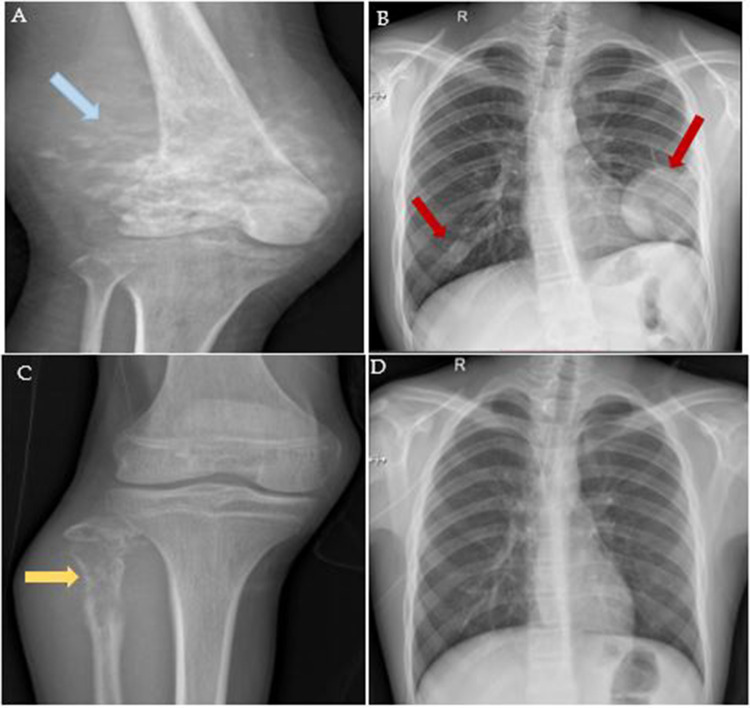

Methods: 150 patients diagnosed with osteosarcoma were selected between 2009 and 2019 from the Shaukat Khanum Memorial Cancer Hospital and Research Centre, Lahore, Pakistan. FFPE tissue samples of primary tumors and metastatic lesions were retrieved to conduct immunohistochemical analysis. Moreover, the clinicopathological data of these patients were gathered from the hospital information system.

Results: Out of 150 patients, primary tumors were accessible for 134 individuals, while metastatic lesions were available for 49 patients. IDO expression was identified in 9 (6.71%) primary tumors and 2 (4.08%) metastatic lesions among osteosarcoma patients. Furthermore, 3 patients exhibited high expression (27.3%), while 8 displayed low IDO expression (72.7%).